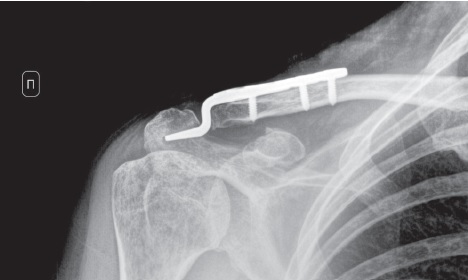

Идентичное по высоте смещение центрального отломка ключицы с клювовидным отростком лопатки позволяло косвенно судить об интактных ключично-клювовидных связках. На наш взгляд, предпочтительным имплантатом для решения данной задачи была и остается крючковидная пластина (hook-plate). В первые сутки госпитализации пациентке была выполнена операция: открытая репозиция отломков, фиксация крючковидной пластиной с винтами. Во время выполнения операции на основании рентгеноконтроля было принято окончательное решение не фиксировать дополнительно клювовидный отросток лопатки (рис. 2).

Рис. 2. Интраоперационная рентгенограмма правого акромиально-ключичного сустава в переднезадней проекции: состояние после открытой ручной репозиции отломков, фиксации крючковидной пластиной акромиального конца правой ключицы. Смещение отломков устранено

Fig. 2. Intraoperative X-ray of the right AC joint in AP view after open manual reduction and fixation of the right distal clavicle with a hook plate. Displacement of fragments is eliminated